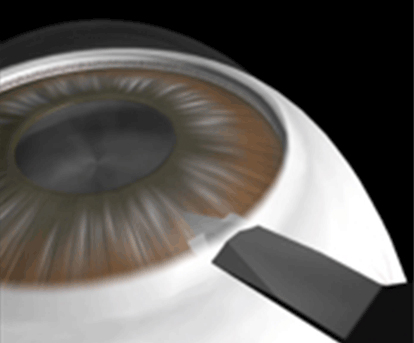

私の白内障の術式をシェーマで説明を致します。

強角膜耳側より、2.0-2.4mm切開しております。